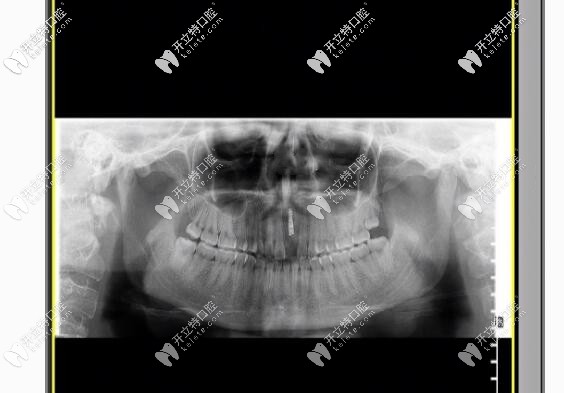

幸好我找對(duì)了醫(yī)院和醫(yī)生,醫(yī)生給我的建議是拆除烤瓷牙,換上瑞士iti或瑞典nobel種植牙,幾番考慮之后,我選擇的是瑞士iti種植牙,有利于骨愈合,還不用進(jìn)行二期手術(shù)什么的,我給忘了,也正好趕上美奧口腔有活動(dòng),價(jià)格優(yōu)惠的狠喲!